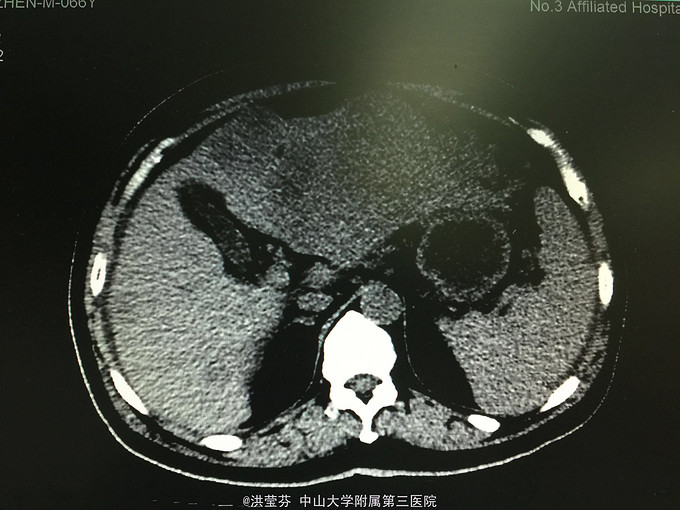

查体:上腹部轻压痛,无反跳痛。 辅助检查:上腹部CT增强提示:肝S2/3/4段恶性肿瘤,肝内多发子灶,肝左静脉及门静脉左、右支受侵;腹腔多发转移瘤;肝门部、腹膜后多发肿大淋巴结;门静脉海绵样变;少量腹水。胸部CT提示:1、双肺多发小结节,结合病史,考虑转移瘤;纵膈、双侧肺门多发肿大淋巴结。2.双肺炎症;左侧胸腔少量积液。CA125 555.1IU/nl,CA199 1093.5IU/nl。

诊断考虑胆管细胞癌可能性大,予完善肝穿刺,活检病理示:符合中分化腺癌,胆管细胞癌可能性大。免疫组化结果示:Hep(-),CK(+),CK19(+),CEA(-),CDX-2(-),DK20(-),Ki 67(约15%),TTF-1(-)。诊断明确肝内胆管细胞癌,IV期,无明显化疗禁忌,予GP方案化疗,辅以护胃、护肝、止吐等治疗。

2程化疗后复查CT评价疗效疾病进展,并腹水明显增多,予加强支持治疗后予改行减量FOLFOX方案化疗,过程顺利。患者精神较差,症状上改善不明显,预后差。 这种情况大家还有什么治疗方案可以推荐的吗?